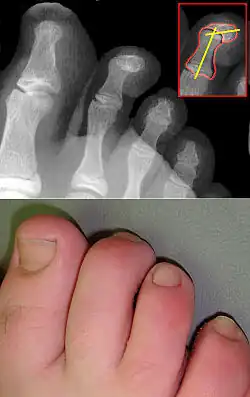

Röntgenbilder

-

Hammerzehen vor einer operativen Korrektur -